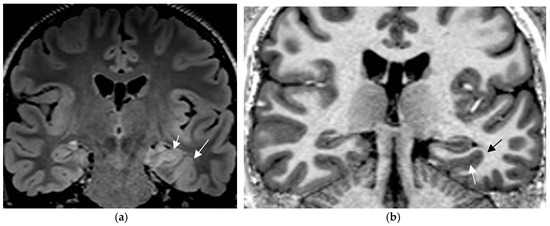

4.3. Expert Readers Take Advantage of the Added Value of an Epilepsy Specific Protocol

In a prior study [67] and in a recent prospective evaluation of the HARNESS protocol [68] in 123 and 131 patients, the sensitivity of MRI was particularly enhanced through interpretation by experienced readers for the diagnosis of hippocampal sclerosis and focal cortical dysplasia as the previously most frequently missed entities in adults and children, respectively. The combination of a dedicated MR and expert reader assessment increased detection of hippocampal sclerosis from 18 to 45% and of focal lesions from 50 to 91% [67]. Expert readers are more likely to recognize focal hippocampal sclerosis (Figure 2) and detect associated indirect signs such as atrophy of the ipsilateral fornix and mammillary body. Observations like the transmantle sign and subtle changes to adjacent white matter in focal cortical dysplasia and periventricular nodular and subcortical band heterotopia are challenging and less likely to be missed visually by an experienced reader.

Hippocampal sclerosis depicted on coronal FLAIR (a) and T2 w sequence (white arrows) (b) (1.7 mm each) with volume reduction of the CA1-4 regions of the left hippocampus. FLAIR and T2 signal increases and slight atrophy of the left fornix (short arrow in (b)). Marked volume reduction of left temporal lobe as evidenced by the lower position of the left Silvian fissure (long arrow in (b)) compared to the right side.